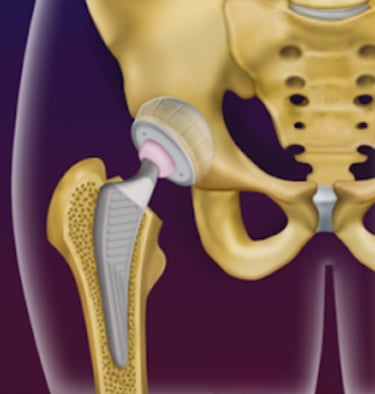

Imagens dos liners dupla-mobilidade e constrito, usados em pacientes com alto risco de luxação ou em pacientes com luxações recorrentes na prótese.

Entretanto, caso as luxações ocorram repetidamente, uma nova cirurgia deve ser realizada, para trocar o posicionamento da prótese, caso ele não esteja adequado, e seja a causa das luxações, ou para colocação dos liners dupla-mobilidade ou constritos, que aumentam a estabilidade da prótese e evitam essa complicação.